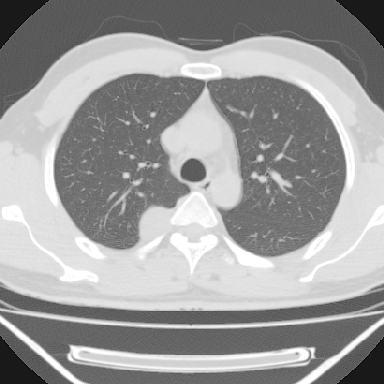

m 30 右胸痛10年

m,30岁,右胸痛10年。

右上后纵隔旁软组织肿块影,与肺界面光滑,与胸壁呈钝角相交,提示肺外病变。位于肋骨下缘,边缘清楚,呈三角样指向与右侧椎间孔,但并示进入椎间孔;与对侧神经根对比,属同一走行方向。

考虑后纵膈良性肿瘤,神经源性肿瘤可能大。

鉴别:胸膜来源肿瘤。影像表现虽有肺外征象,但无胸水等相应佐证;再者,病史前10年,超长,与胸膜肿瘤不太吻合。

建议:再次查体,问清疼痛部位,如为1~2个肋间痛则神经源性肿瘤可能大,如疼痛较弥散,不按肋间分布,则可能为后纵膈其它来源肿瘤。